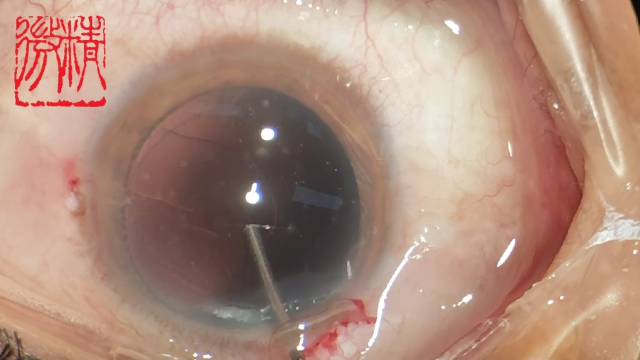

大瓜:湖南省人民医院副院长出轨眼科主任?

号外号外,湖南省人民医院副院长祖雄兵和眼科主任医师曾琦被指存在不正当关系,并有不雅视频传出。对此,医院工作人员回应:组织正在调查,请给医院宣传部门联系。当地卫生健康委员会对此回应:暂未接到相关的信访反映。祖雄兵为湖南省人民医院副院长,泌尿外科学科带头人。曾琦,博士,主任医师,硕士研究生导师。现任湖南省人民医院眼科副主任、眼科一病区主任,湖南省卫生健康高层次青年骨干人才,湖南省预防医学会眼病防治专业委员会主任委员、湖南省女医师协会眼科专业委员会主任委员、湖南省医学会眼科学专业委员会防盲学组副组长、湖南省医学会眼科学专业委员会眼外伤及职业病学组副组长、湖南省医学会眼科学专业委员会白内障学组副组长、